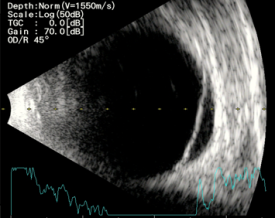

게다가 우안에는 다음과 같은 3가지 심각한 문제가 발견되었습니다.

3) 망막박리

우선 백내장 상태가 더 심한 우안을 먼저 수술하기로 합니다.

이땐 수술 중 언제든 수정체낭이 터지거나 모양체소대가 끊어질 수 있기 때문에,

공막고정술로 전환할 가능성을 염두에 두고 수술을 진행해야 합니다.

(백내장수술 후 망막이 보이면 망막박리도 정도에 따라 수술방법을 정해야 했죠.)

우안은 0.1 (망막박리 수술 시 실리콘 주입 상태),